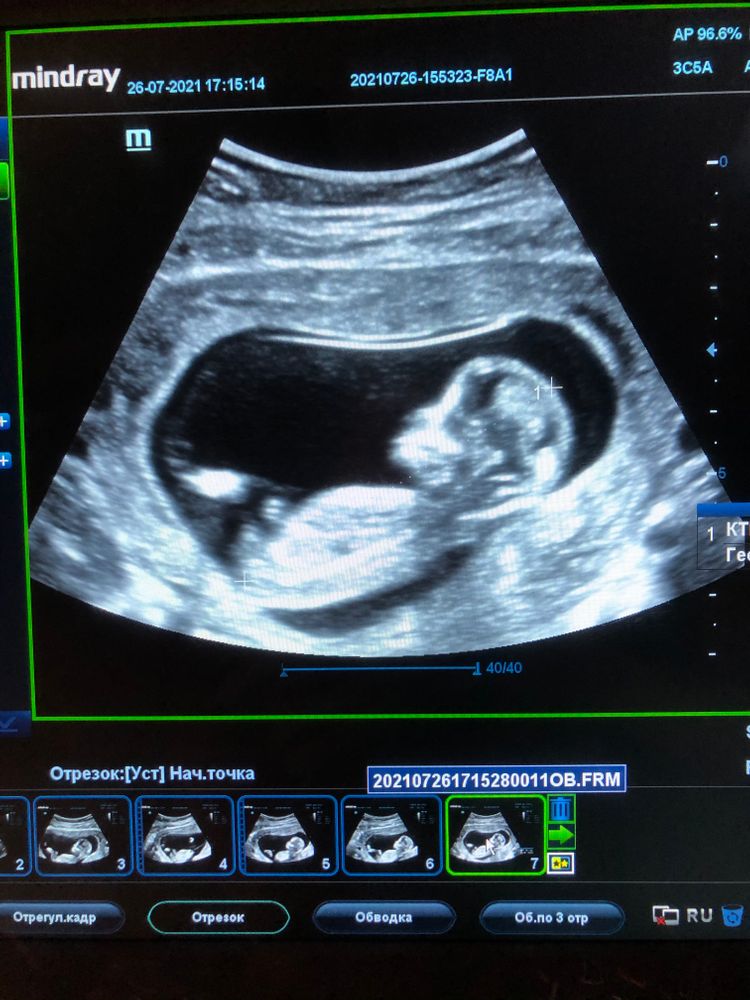

УЗИ, КТГ, доплерСегодня сходила на узи по определению пола, сказали, что будет девчуля,👧 гадания по методу Рамзи и половому бугорку на мне не сработали🤷🏻♀️ Завтра отправлюсь к другому узисту по показаниям, кровит с 13 недели. Думаю завтра уж точно будет известно, кто ж у нас в пузике💕

это фото, сделанное сегодня